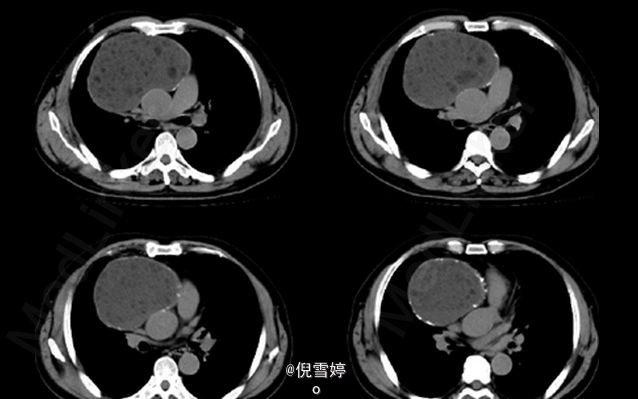

患者,男,49岁岁,因胸部不适2d就诊

患者除胸部不适外并无其他明显症状 辅查CT,右前纵隔囊性占位,多发脂肪样密度,病理检查良性

畸胎瘤 处理:手术切除